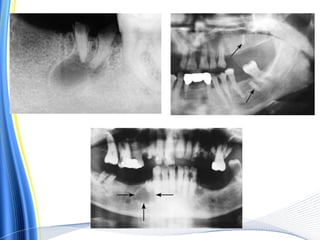

 PREOPERATIVE RADIOGRAPHS –

Indications

i. H/O difficult & attempted extractions

ii. Resistance to forcep extraction

iii. Planning to remove the tooth by dissection

iv. Close approximation with important anatomical structures

v. Abnormal root pattern – third molars, in standing premolars, misplaced canine

vi. Tooth having periodontal problem & some sclerosis – hypercementosis

vii. Trauma to tooth – fracture of tooth, roots & alveolar bone

viii. Isolated & Unopposed maxillary molars

ix. Partially erupted, unerupted tooth & retained roots

x. Delayed erupting or having abnormal crown

xi. Condition indicating dental or dentoalveolar deformities –

osteitis deformans - hypercementosis

cleido-cranial dysosteosis - hooked root

therapeutic irradiation

osteopetrosis